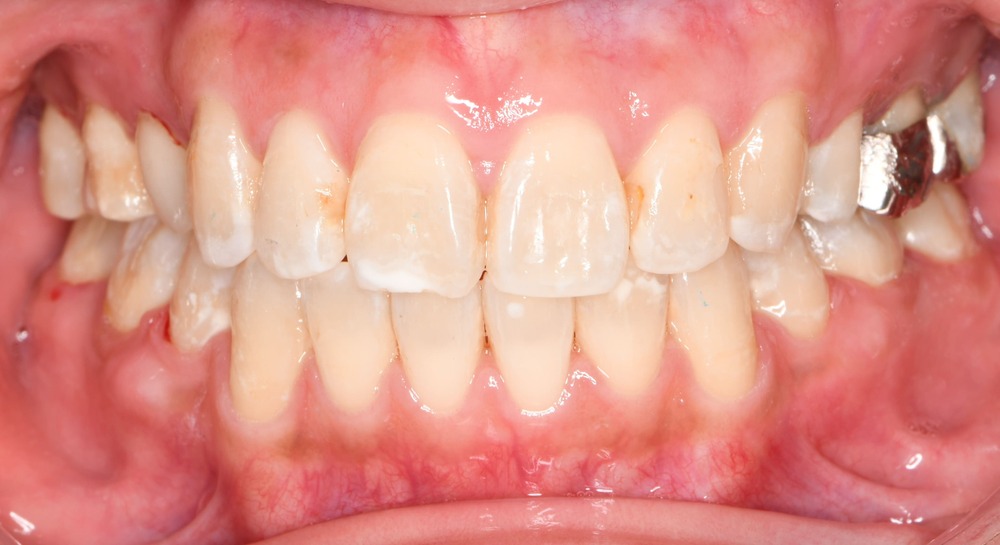

正面(口腔内)

開咬が完全に改善

上下の叢生も整い、理想的なアーチフォームに